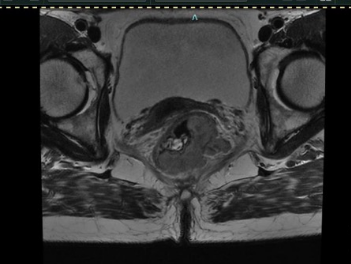

本次參賽病例為一例直腸神經(jīng)內(nèi)分泌癌伴肝轉(zhuǎn)移病灶的老年女性患者,影像科專家評(píng)估分期T3cN1M1,外科專家評(píng)估患者暫無(wú)手術(shù)指征,經(jīng)與腫瘤內(nèi)科專家和放療科專家行MDT會(huì)診后,予患者先行化療?;颊呋驒z測(cè)外送結(jié)果提示患者敏感性較高的化療藥物為:伊立替康和卡培他濱?;颊咝幸晾婵?FU+亞葉酸鈣+貝伐單抗治療4周期后,病情評(píng)估為穩(wěn)定,后患者至放療科行卡培他濱化療聯(lián)合直腸原發(fā)灶局部放療,直腸原發(fā)灶獲得影像學(xué)部分緩解。后患者出現(xiàn)腹主動(dòng)脈旁新發(fā)腫大淋巴結(jié)。再次行病理科、影像科、腫瘤內(nèi)科和放療科多學(xué)科協(xié)作診療,考慮患者為神經(jīng)內(nèi)分泌癌,根據(jù)2023歐洲神經(jīng)內(nèi)分泌腫瘤學(xué)會(huì)推薦轉(zhuǎn)移性消化系統(tǒng)NEC治療以順鉑聯(lián)合依托泊苷為主。并且神經(jīng)內(nèi)分泌癌2024 CSCO指南推薦對(duì)于既往接受過(guò)系統(tǒng)治療且持續(xù)進(jìn)展、缺乏標(biāo)準(zhǔn)治療的轉(zhuǎn)移性NEC患者,也可考慮免疫治療。因此,予患者行依托泊苷聯(lián)合順鉑治療,并且聯(lián)合索凡替尼和恩沃利單抗。兩周期用藥后復(fù)查示腹主動(dòng)脈旁新發(fā)腫大淋巴結(jié)較前明顯縮小,其余病灶穩(wěn)定。 初治時(shí) 直腸病灶放療后出現(xiàn)新發(fā)腹主動(dòng)脈淋巴結(jié) 治療后肝臟病灶穩(wěn)定,直腸原發(fā)灶和腹主動(dòng)脈腫大淋巴結(jié)明顯縮小 王明 主任醫(yī)師 乳腺與腹部腫瘤放療科(放療一科)主任 專業(yè)擅長(zhǎng):各種胸部腫瘤:如乳腺癌、食管癌的放化療、免疫、靶向治療,以及各種腹部腫瘤的放化療,尤其擅長(zhǎng)各種消化道腫瘤:胃癌、肝癌、膽管癌、胰腺癌、結(jié)直腸癌的放療、化療、靶向等綜合治療。泌尿系腫瘤:腎癌、膀胱癌、前列腺癌等腫瘤的綜合治療。 張一擎 主治醫(yī)師 滄州市中心醫(yī)院乳腺與腹部腫瘤放療科(放療一科) 苗玉 副主任醫(yī)師 滄州市中心醫(yī)院病理科 專業(yè)擅長(zhǎng):消化系統(tǒng)腫瘤及消化道早癌篩查病理診斷。 孫敏 副主任醫(yī)師 磁共振成像科 從事臨床工作十多年,對(duì)臨床常見(jiàn)疾病的核磁診斷有豐富的經(jīng)驗(yàn)。 李哲 副主任醫(yī)師 滄州市中心醫(yī)院腫瘤內(nèi)一科 楊立勝 主治醫(yī)師 滄州市中心醫(yī)院結(jié)直腸肛門外科 專業(yè)擅長(zhǎng):結(jié)直腸癌、肛周常見(jiàn)疾病、盆底疾病的外科診療。